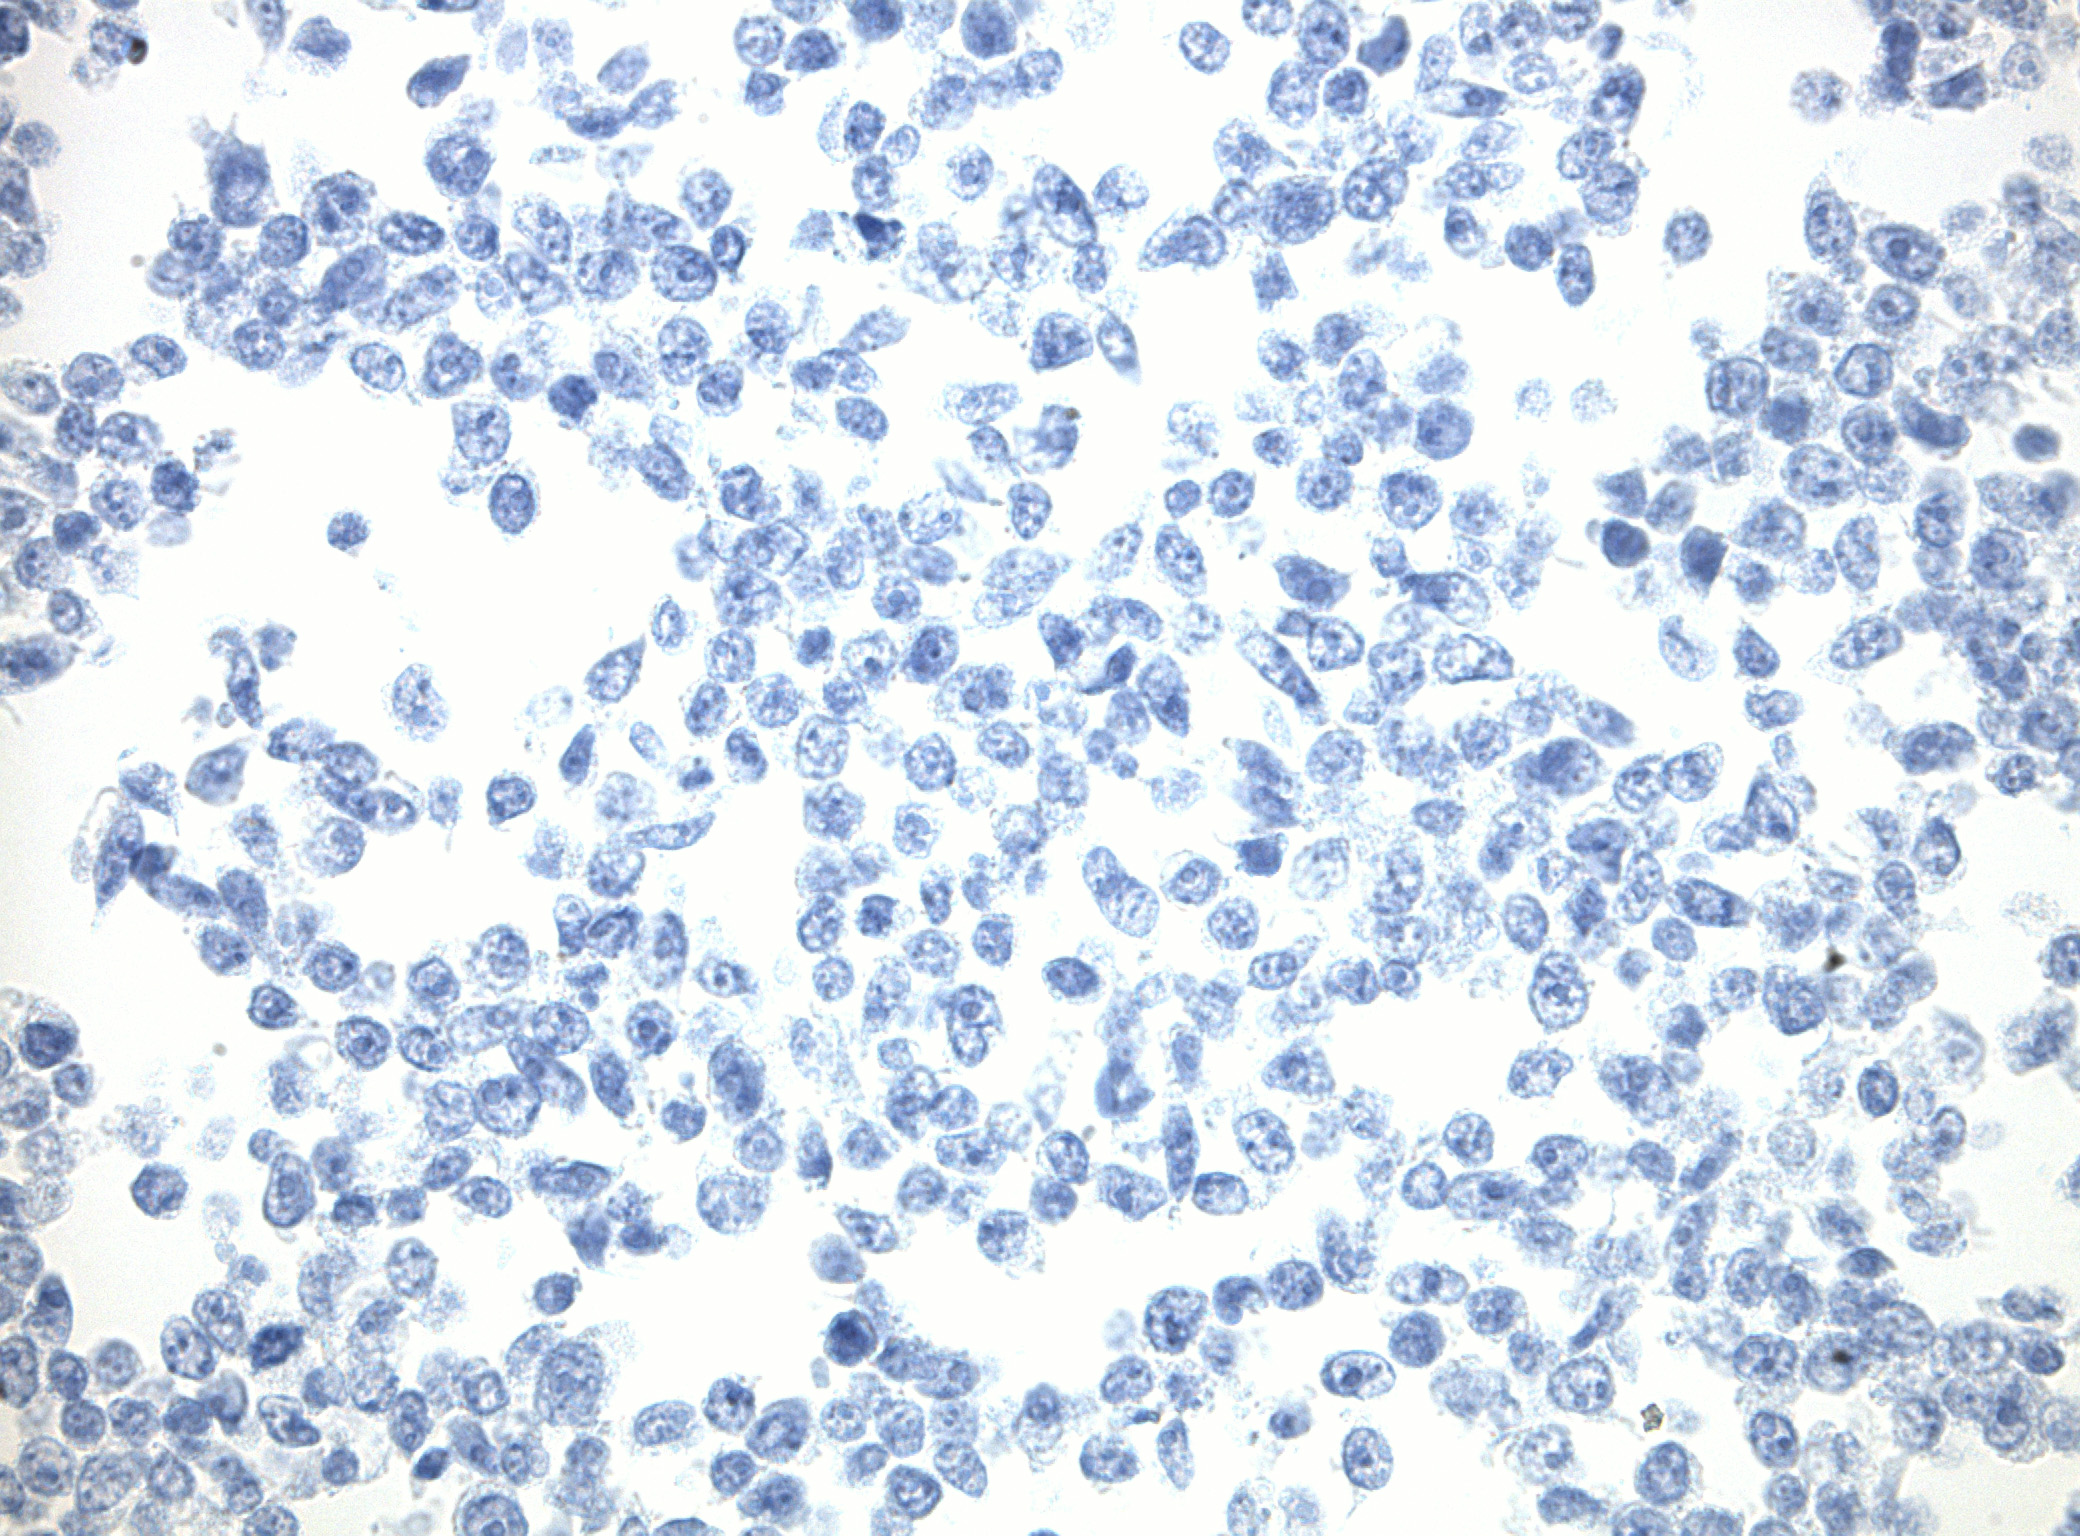

IDH1 (R132H) Mutant-Specific Antibody Screening, Validation, and Specificity

CytoSections enables identifying the right antibody for your research. See how CytoSections, featuring WT or mutant IDH1 (R132H) protein, helped screening and validation of specific antibody against the mutant IDH1 (R132H).

|

|

|

|

|

|

CytoSections |

IDH1 (WT) |

IDH1 (R132H) |

IDH1 (WT) |

IDH1 (R132H) |

|

IDH1 (R132H) Antibody |

|

|

||

|

Reactivity |

None |

Strong |

None |

Mild |